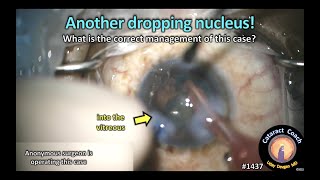

Complicated cataract Surgery: Dropped Nucleus CataractCoach 1437: another dropping nucleus in cataract surgery

CataractCoach 1437: another dropping nucleus in cataract surgery

Complicated cataract Surgery: Dropped Nucleus CataractCoach 1437: another dropping nucleus in cataract surgery

CataractCoach 1437: another dropping nucleus in cataract surgery